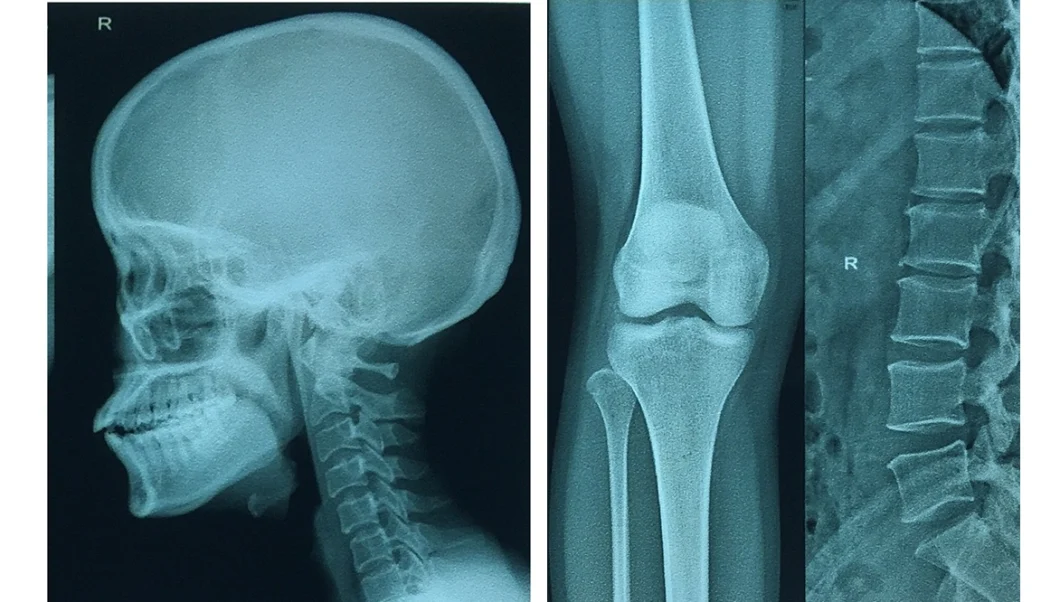

Laser Film for Medical X-ray Image Output Printing Images |